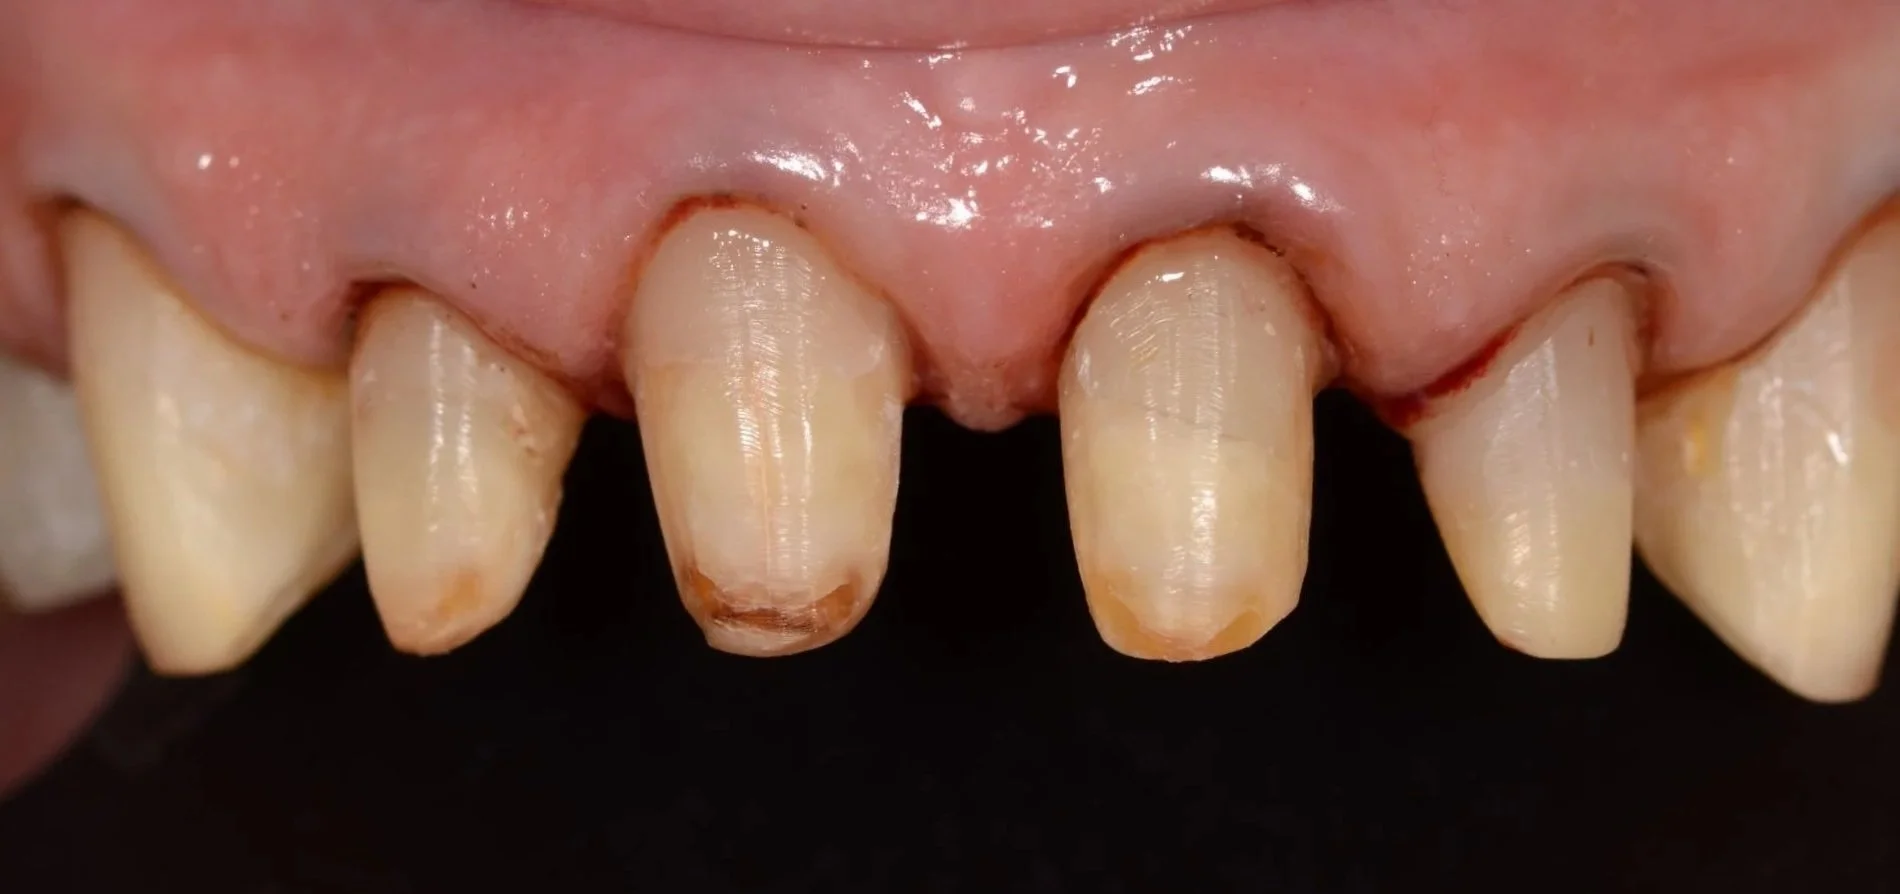

Tallados

Coronas definitivas